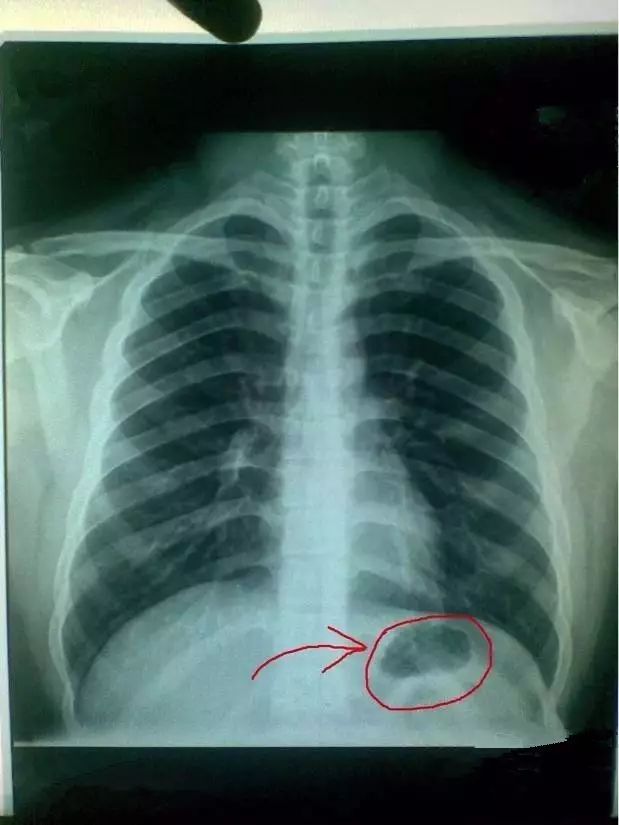

胸片胃部胃泡图,胃泡图片

胸片上的胃泡是什意思?它具体在什么位置,是什么形状的?

(正常胸片,能显示胃泡区的,比如小编本人的胸片) 另一部分气体进入

4岁患儿,因支气管肺炎住院,查胸片发现心尖,胃泡在右边,好羡慕这么与

胸片胃泡很黑很大

胸片上的正常胃泡

胸片上的正常胃泡图片

胸片胃泡大

胸片展示胃泡特别大